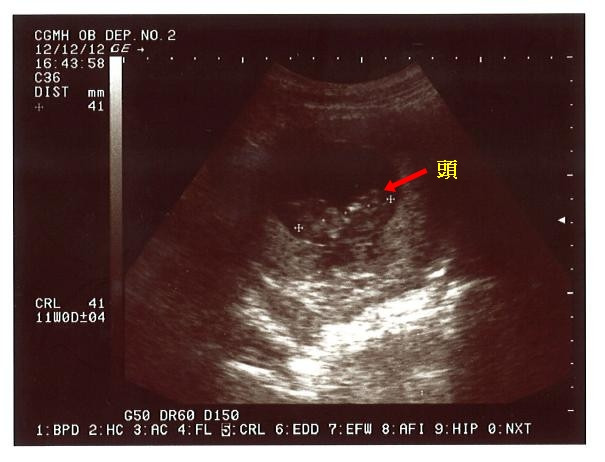

12/12 第一次產檢